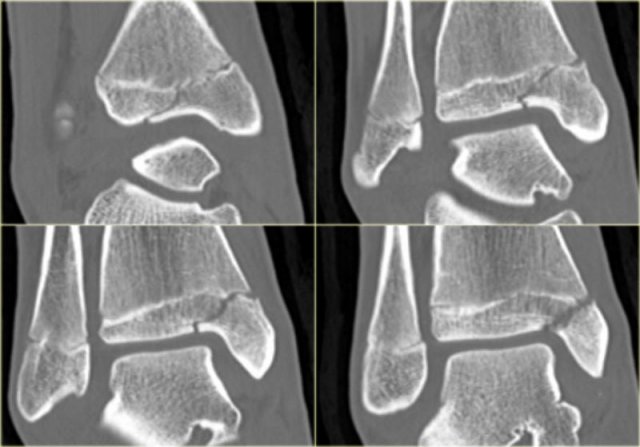

In some cases a fracture of the posterior malleolus is barely or not visible on the radiographs and can only be seen on CT.

First study the radiographs and then continue with the CT.

By the way....there are two fractures.

You can enlarge the images by clicking on them.

The CT shows an avulsion of the tertius at the insertion of the posterior syndesmosis (red arrows).

The alignment is so perfect, that you do not see the fracture on the radiographs.

Maybe the fracture is seen on the AP-view as indicated by the red arrows, but this is questionable.

Notice that there is also an avulsion at the tibial insertion of the anterior syndesmosis, i.e. Tillaux fracture.

This combination of findings implicate that the ankle is unstable.

A syndesmotic screw has to be inserted.